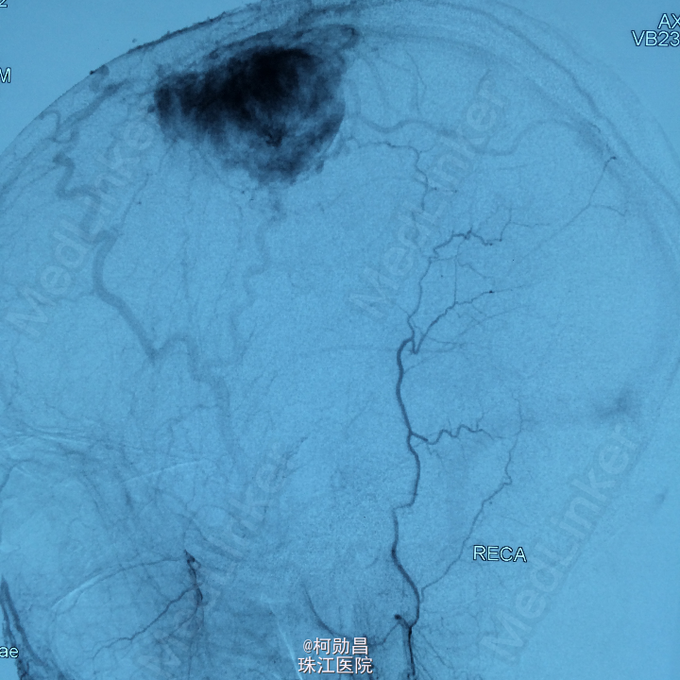

诊断:左侧顶叶占位 处理:行DSA检查,提示肿瘤染色,予PVA颗粒行血管内栓塞治疗。

术后再予开颅手术治疗,书中见供血动脉闭塞,出血量少。